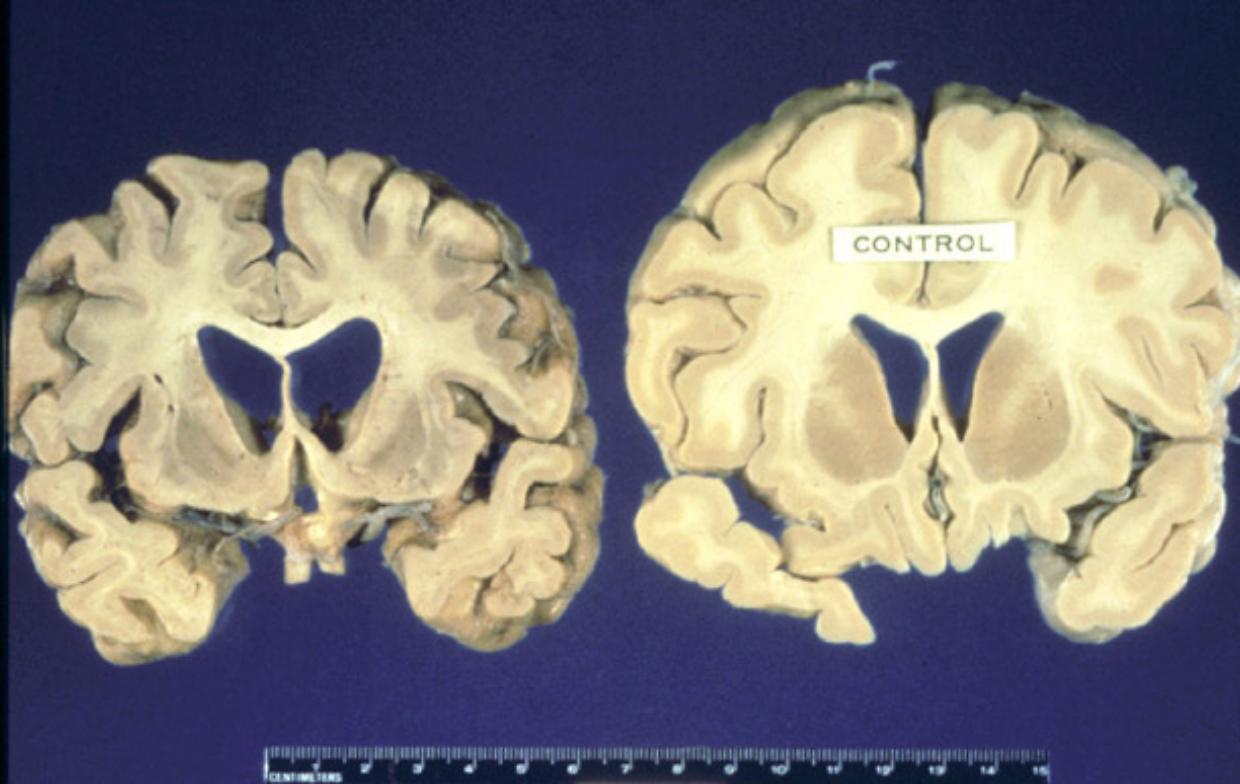

Le encefalopatie spongiformi trasmissibili sono malattie degenerative e letali che colpiscono soprattutto il cervello. Si sviluppano quando una proteina, la PrP, assume una forma anomala trasformandosi in prione, in grado di contagiare altre proteine e di danneggiare irreversibilmente il tessuto cerebrale.

Secondo gli esperti, esistono tre forme principali: sporadiche, senza cause note; familiari, legate a mutazioni genetiche ereditarie; e acquisite, quando il contagio avviene da un altro organismo. La BSE, nota come morbo della mucca pazza, appartiene a quest’ultimo gruppo ed è stata collegata al consumo di carne contaminata.